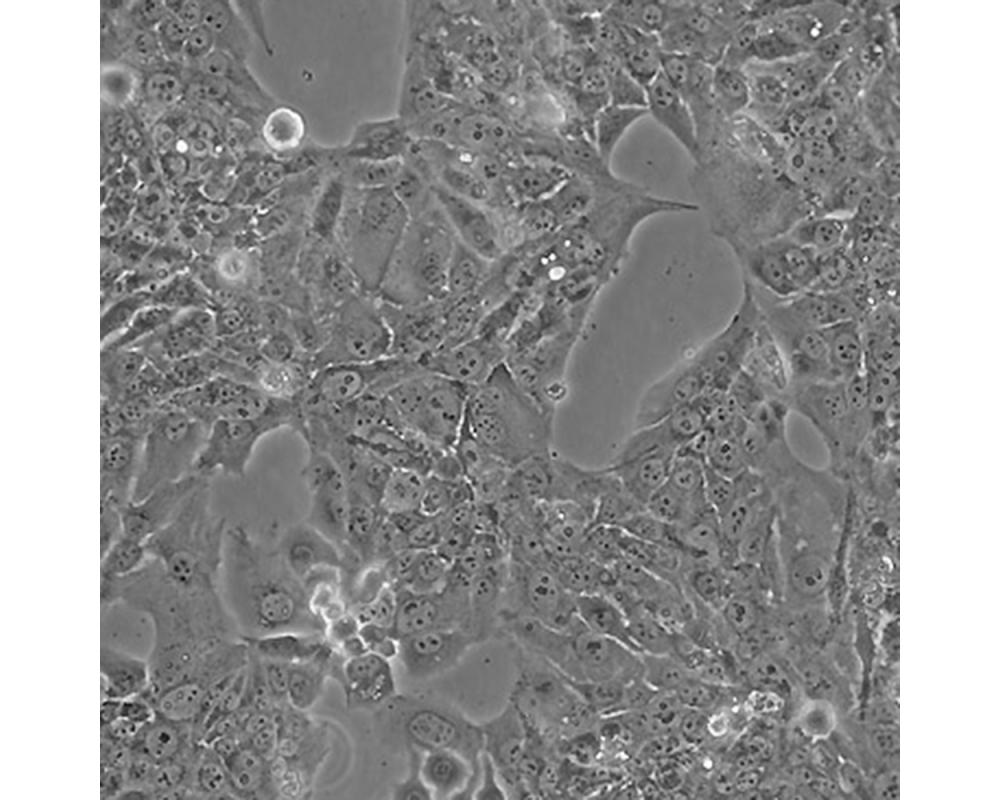

BeWo

中文名稱 人胎盤絨膜癌細胞

組織來源 妊娠性絨癌

形態特征 上皮樣

生長特性 貼壁生長

特征特性 取自人絨癌腦轉移組織,在倉鼠頰囊移植傳代8年。利用移植瘤組織進行體外培養,建立細胞系。利用不同傳代方法建立了不同亞系,JEG-3是其衍生克隆。該細胞可以產生雌激素、孕激素、雌酮、雌二醇、雌三醇、hCG、胎盤催乳素、角蛋白。

培養條件 DMEM(高糖)+10%FBS